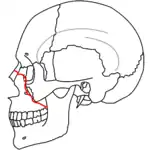

A principios del siglo XX, René Le Fort trazó ubicaciones típicas para las fracturas faciales, éstas ahora son conocidas como I, II y III fracturas de Le Fort (derecha).[5][2][6]

La Fractura de Le Fort#Lefort III, también llamada disyunción craneofacial y fractura facial transversal,[7][11] cruza la parte delantera del maxilar superior e implica al hueso lacrimal, a la lámina papirácea, y a la cavidad orbitaria, y a menudo implica al hueso etmoides,[9] es la más grave.[12] Las fracturas de Le Fort, que representan del 10% al 20% de las fracturas faciales, a menudo son asociadas con otras lesiones graves.[9]

Le Fort hizo sus clasificaciones basadas en el trabajo con cráneos de cadáveres, y el sistema de clasificación ha sido criticado por impreciso y simplista ya que la mayoría de las fracturas del tercio medio facial implican una combinación de las fracturas Le Fort.[9] A pesar de que la mayor parte de las fracturas faciales no siguen los patrones descritos por Le Fort de forma precisa, el sistema todavía se utiliza en la clínica para clasificar las lesiones.[13]